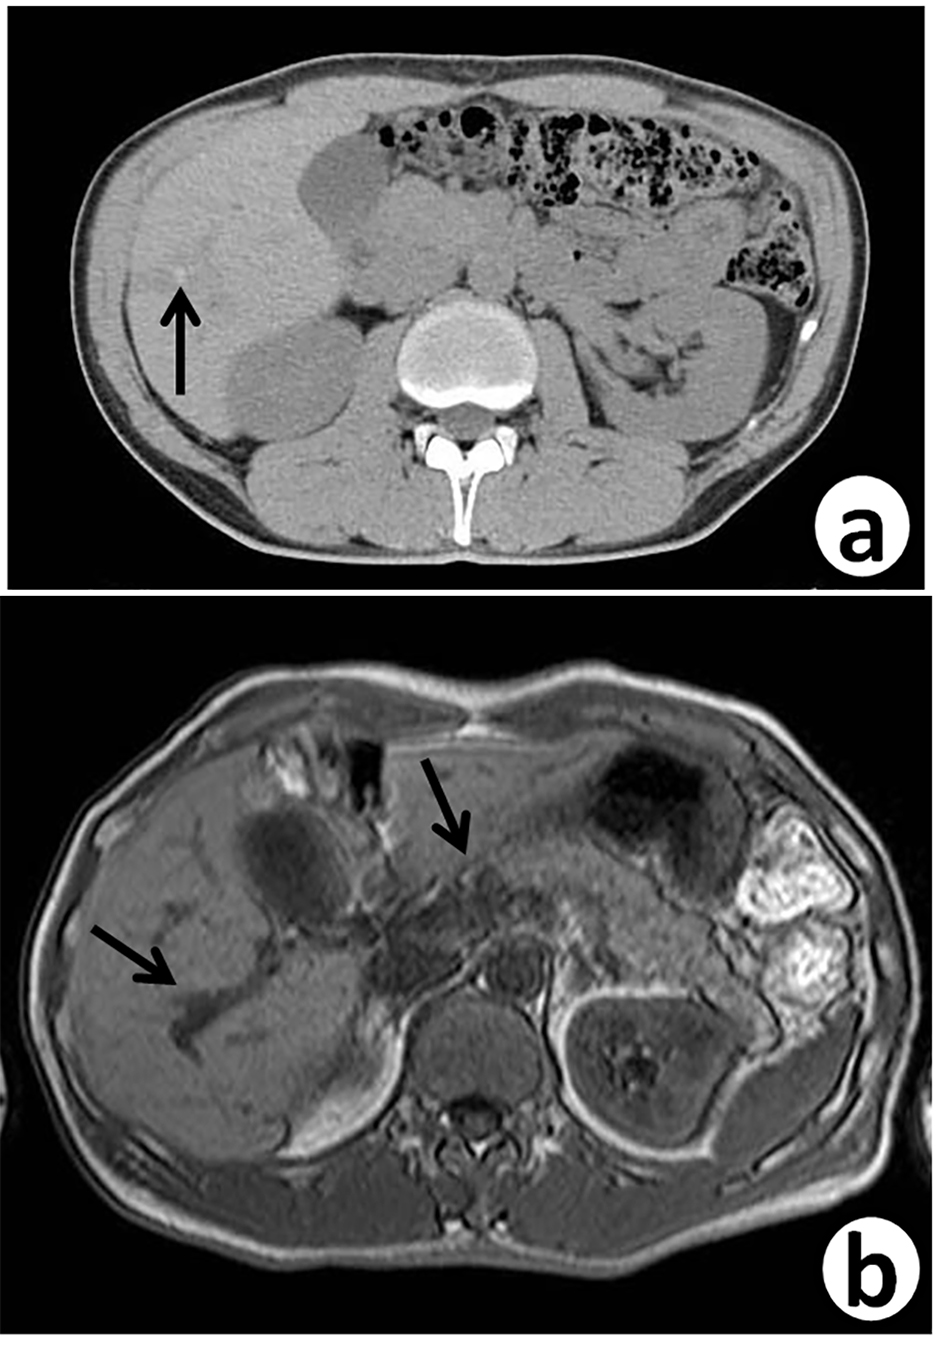

Seven years ago, a 51-year-old Japanese man received sigmoidectomy for the treatment of sigmoid colon cancer (stage I). It was histopathologically moderately differentiated adenocarcinoma (tub2, Fig. 1). He was intensively followed up after the operation. He was well controlled for his diabetes mellitus in Department of General Medicine of our hospital. On November 16, 2015, slight elevation of serum enzymes, alkaline phosphatase (ALP, 352 IU/L; normal range, 104 - 338 IU/L) and γ-glutamyltransferase (γ-GT, 160 IU/L; normal range, 0 - 47 IU/L) of hepatobiliary system was noted. A tumor marker, CEA (5.2 ng/mL; normal range, 0 - 4.9 ng/mL), was slightly elevated. Follow-up CT (Fig. 2a) and MRI (Fig. 2b) examinations revealed dilatation of small intrahepatic bile duct in the S5/6 area, suggesting intrahepatic cholangiocarcinoma or metastatic tumorous lesion. Clinical diagnosis based on the image analysis was intrahepatic cholangiocarcinoma or liver metastasis of CRC.

![]() Click for large image | Figure 2. Follow-up abdominal contrast-enhanced CT scan (a) and MRI-T2 (b), 7 years after sigmoidectomy, reveal small dilated intrahepatic bile ducts (arrows) with thickening in the S5/6 area. |